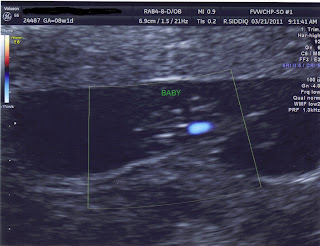

.......We found out that BABY # 3 is on it's way! I'm pregnant again and due October 31st! Yep, a Halloween baby! I am 8 weeks and 1 day today. I had an ultra sound this morning and we saw a beautiful heartbeat of 157 bpm.

The blue blob is the heart beat. They turned on the doppler to see the blood flow. The baby is measuring right on track!